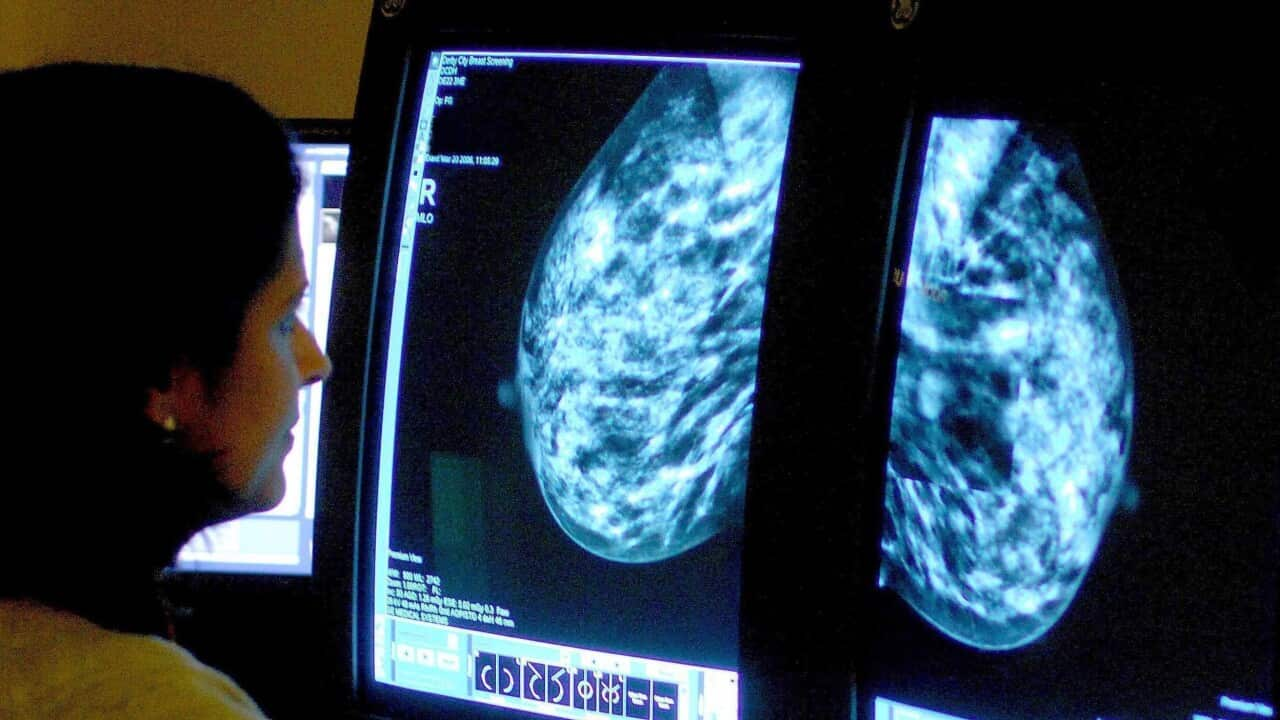

Despite having a mammogram six months earlier her GP scheduled an ultrasound which showed two suspicious lumps.

"I try to impart the importance of also having ultrasounds, particularly for women with dense breast tissue. The mammogram didn't show the cancer but it could be seen on an ultrasound or MRI," she said.